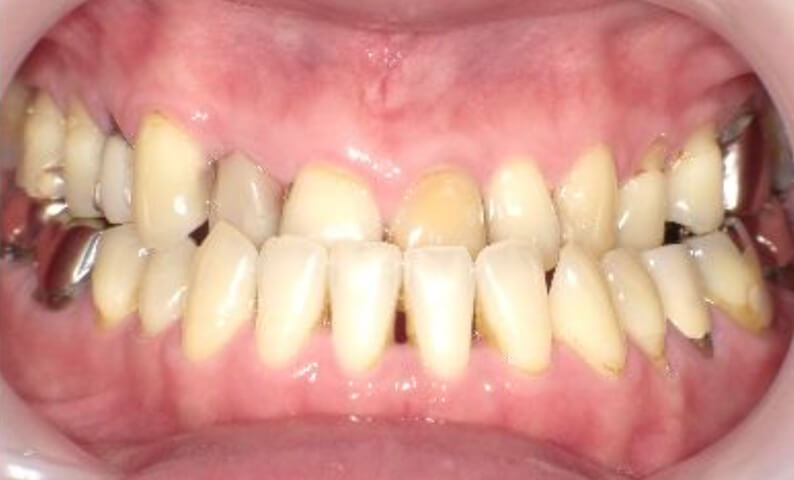

症例_003 下顎だけの部分矯正

治療期間:10ヶ月金額:24万円+税女性前歯のガタガタ下の前歯だけ上顎は補綴治療中

| Before | After |